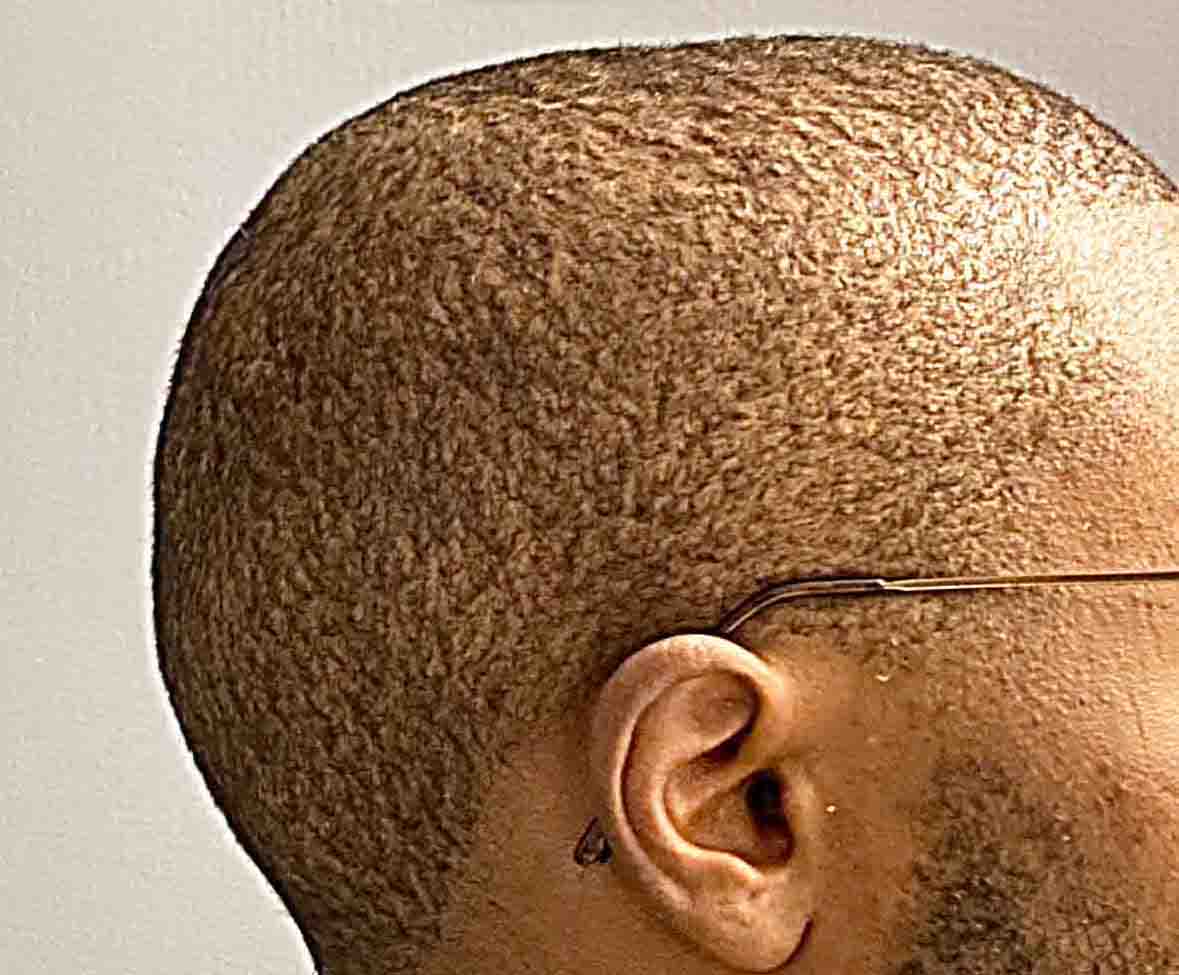

Patient 100

Desire for reshaping of an asymmetric flat back of the head in a shaved head male.

A combined back of the head reshaping procedure was done with a custom skull implant, sagittal ridge reduction and a right temporal muscle reduction.

Desire for reshaping of an asymmetric flat back of the head in a shaved head male.

A combined back of the head reshaping procedure was done with a custom skull implant, sagittal ridge reduction and a right temporal muscle reduction.